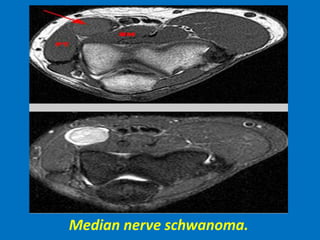

Soft tissue masses about the elbow joint.

Median nerve schwanoma.